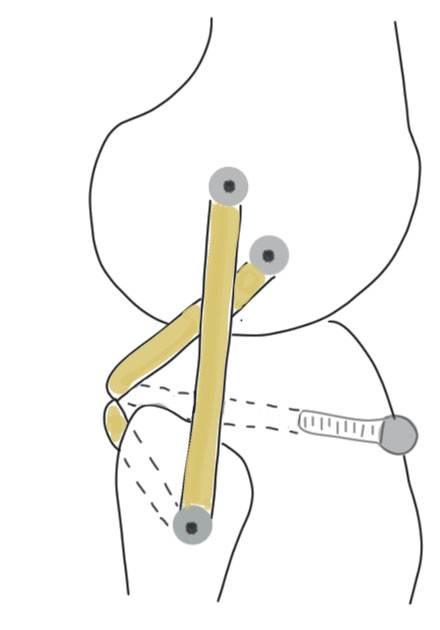

B. Larson Loop

Concept

- single fibular tunnel as per LaPrade

- single LCL tunnel

- two limbs of graft to constitute LCL and popliteofibular

- pull both limbs into femoral tunnel and secure with screw